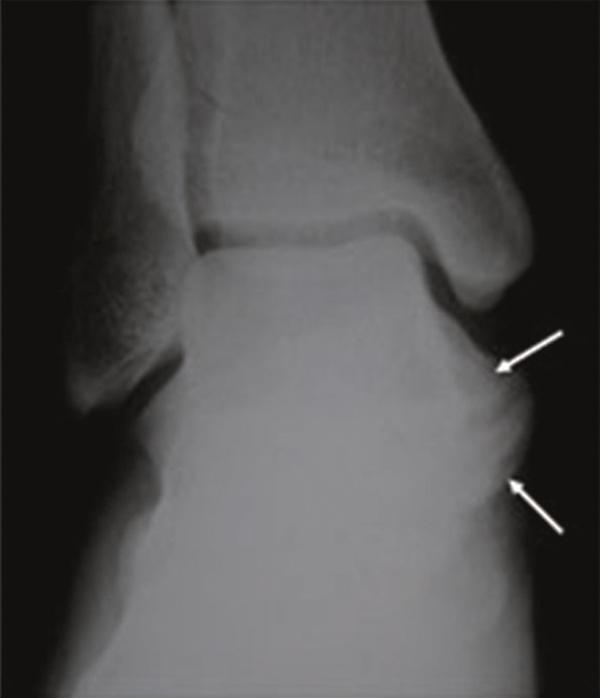

We report the clinical and radiologic findings of a calcaneal osteochondroma with an extremely rare placement and painfull, rapid reccurence following surgical excision in a skeletally mature female. The lesion showed growth the first-operation later and was re-operated. Histopathological examination did not show malignancy.

我们报告了一名骨骼成熟女性跟骨骨软骨瘤的临床和影像学表现,该肿瘤位置极其罕见,手术切除后疼痛且迅速复发。病变在首次手术后出现生长并再次接受手术。组织病理学检查未显示恶性。